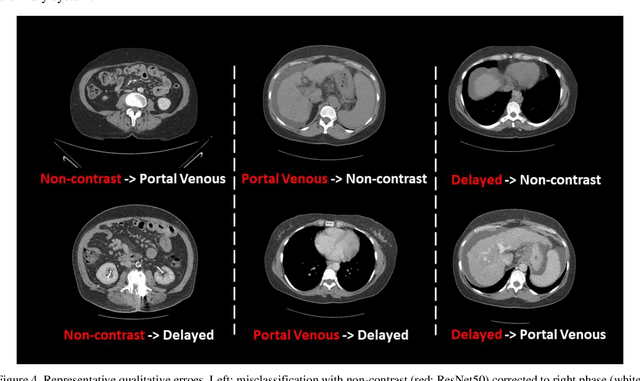

Abstract:Dynamic contrast enhanced computed tomography (CT) is an imaging technique that provides critical information on the relationship of vascular structure and dynamics in the context of underlying anatomy. A key challenge for image processing with contrast enhanced CT is that phase discrepancies are latent in different tissues due to contrast protocols, vascular dynamics, and metabolism variance. Previous studies with deep learning frameworks have been proposed for classifying contrast enhancement with networks inspired by computer vision. Here, we revisit the challenge in the context of whole abdomen contrast enhanced CTs. To capture and compensate for the complex contrast changes, we propose a novel discriminator in the form of a multi-domain disentangled representation learning network. The goal of this network is to learn an intermediate representation that separates contrast enhancement from anatomy and enables classification of images with varying contrast time. Briefly, our unpaired contrast disentangling GAN(CD-GAN) Discriminator follows the ResNet architecture to classify a CT scan from different enhancement phases. To evaluate the approach, we trained the enhancement phase classifier on 21060 slices from two clinical cohorts of 230 subjects. Testing was performed on 9100 slices from 30 independent subjects who had been imaged with CT scans from all contrast phases. Performance was quantified in terms of the multi-class normalized confusion matrix. The proposed network significantly improved correspondence over baseline UNet, ResNet50 and StarGAN performance of accuracy scores 0.54. 0.55, 0.62 and 0.91, respectively. The proposed discriminator from the disentangled network presents a promising technique that may allow deeper modeling of dynamic imaging against patient specific anatomies.